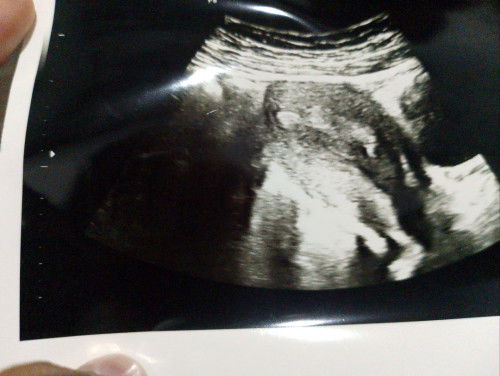

Assalamualaikum bagi pengetahuannya bumil" semua q Maret keguguran Agustus ini telat haid seminggu Hpht 16 juli 2025 ditespek positif Flek cuma 2 hari Ketika USG katanya belum kelihatan dan rahim belum bersih bekas keguguran Padahal Di USG sebelumnya rahimnya sehat bersih pikiran jadi overthinking kemana mana, takut🥺🥺#mohonbantujawabbunda #firstmom